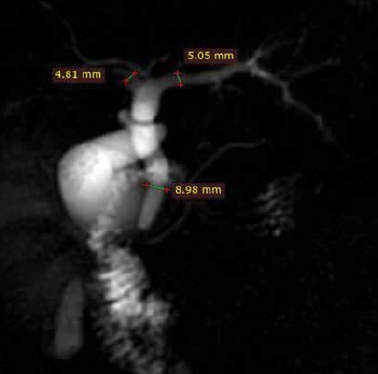

Paciente del sexo femenino de 58 años que acudió al servicio de urgencias por presenar un cuadro de dolor abdominal localizado en el epigastrio, transfictivo. Los estudios de laboratorio mostraron elevación de bilirrubinas a expensas de la bilirrubina directa.

Figura 1 Colangio resonancia; muestra la vía biliar intra y extrahepática, donde existe ausencia de señal en la desembocadura del colédoco así como en zonas del interior de la vesícula biliar.